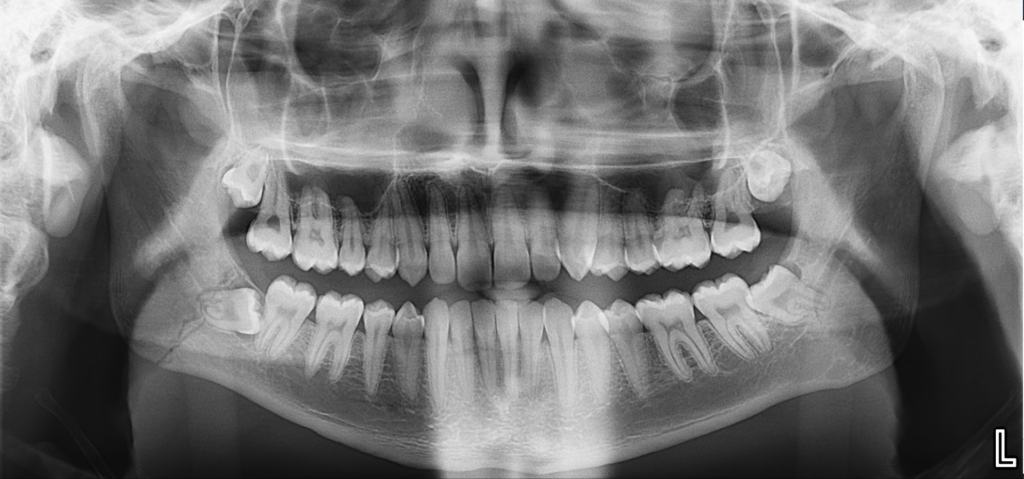

A la evaluación de la tomografía volumétrica (CBCT) en los cortes tangenciales (Figura 2) y transaxiales (Figura 3), se aprecia imagen línea de fractura desde cima de reborde alveolar en zona retromolar derecha hasta zona anterior del ángulo mandibular, así mismo, se observa ligera separación de segmentos óseos desde la zona apical de pieza 48 hasta la basal mandibular, comprometiendo conducto

dentario inferior

CORTES TANGENCIALES

CORTES TRANSAXIALES